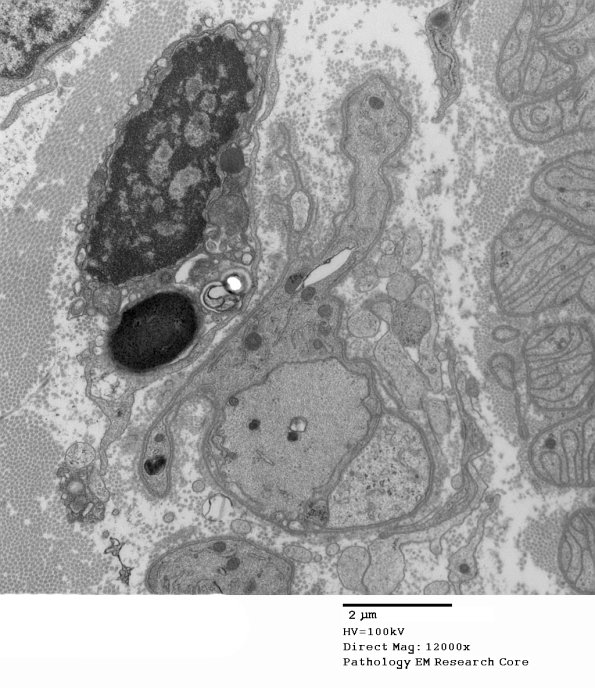

Demyelinated axons without remyelination. Notice there is no myelin debris in the surrounding Schwann cell. (electron micrograph)